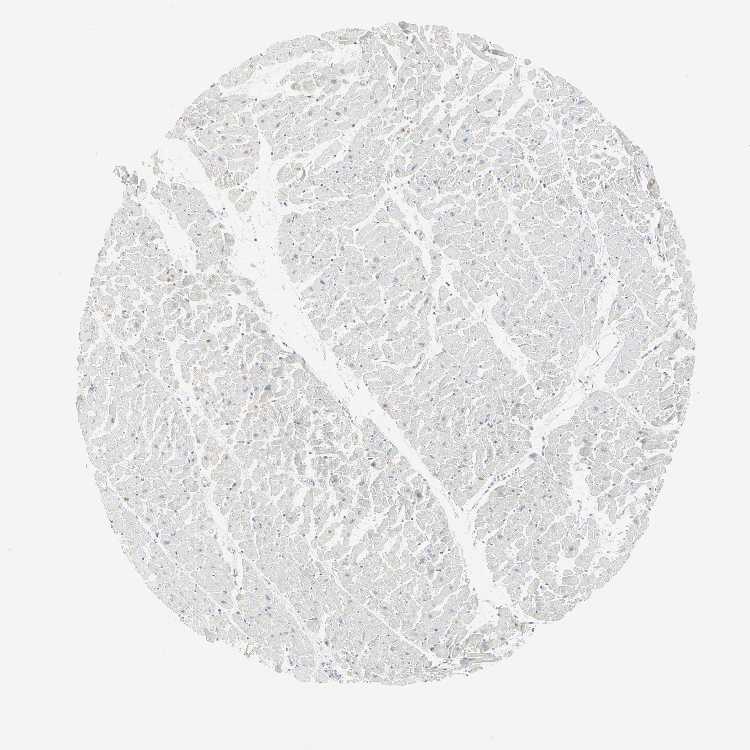

TISSUE PRIMARY DATA HEART MUSCLE Show tissue menu

Heart muscle

Heart

HEART MUSCLE - Expression summary

Protein expression

Heart musclei

On the top, protein expression in current human tissue, based on all annotated cell types, is reported with the units not detected (n), low (l), medium (m) and high (h). Underneath, protein expression in each annotated cell type are reported using the same units.

Protein expression data is based on knowledge-based annotation. For genes where more than one antibody has been used, a collective score is set.

If knowledge-based annotation could not be performed for a gene, no data is displayed here. View antibody staining data further down this page.

Cardiomyocytes: Low

HEART MUSCLE - Antibody stainingi

Antibody staining in the annotated cell types in the current human tissue is reported as not detected, low, medium, or high, based on conventional immunohistochemistry profiling in selected tissues. This score is based on the combination of the staining intensity and fraction of stained cells.

Each image is clickable and will lead to virtual microscopy that enables deeper exploration of all samples and also displays staining intensity scores, fraction scores and subcellular localization as well as patient and tissue information for each sample.

Antibody HPA005695Antibody CAB022068Antibody CAB035999Antibody CAB080052Antibody CAB080054Antibody CAB080098

Cardiomyocytes Not detectedNot detectedLowLowHighHigh